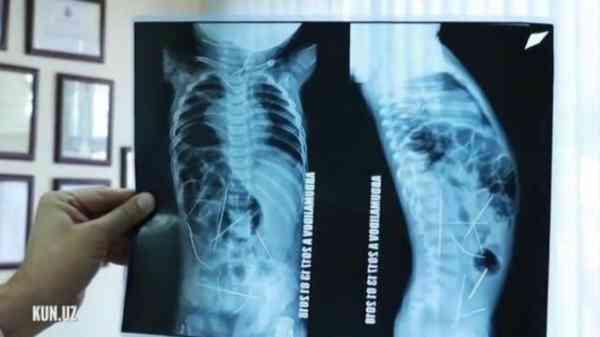

一位11個月大的男嬰因為高燒不退,加上排尿不順,母親便急忙帶著他到醫院求診,醫生原以為是是感染肺炎,但在經過X光檢查後,卻意外發現男嬰體內有16根金屬製長針,畫麵讓人看了頭皮發麻。

長針散布在男嬰的體內各處,包括心臟、脖子、膀胱和脊椎等部位,都能看到長針的蹤影。

醫生也緊急開刀處理,經過9個小時的手術後,順利將他體內的10根針移除,其中有9根是在腹部,另一根則是在脖子。

另外也請來心臟外科醫師,幫忙將靠近心臟處的3根長針也取出,目前男嬰體內還有3根針,近日也將再度接受手術將剩下的針給取出來。